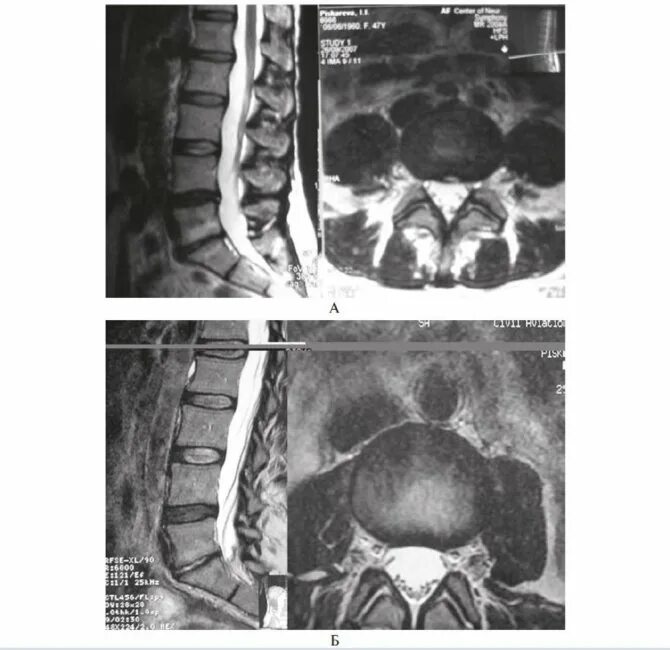

Мрт крестово поясничного отдела